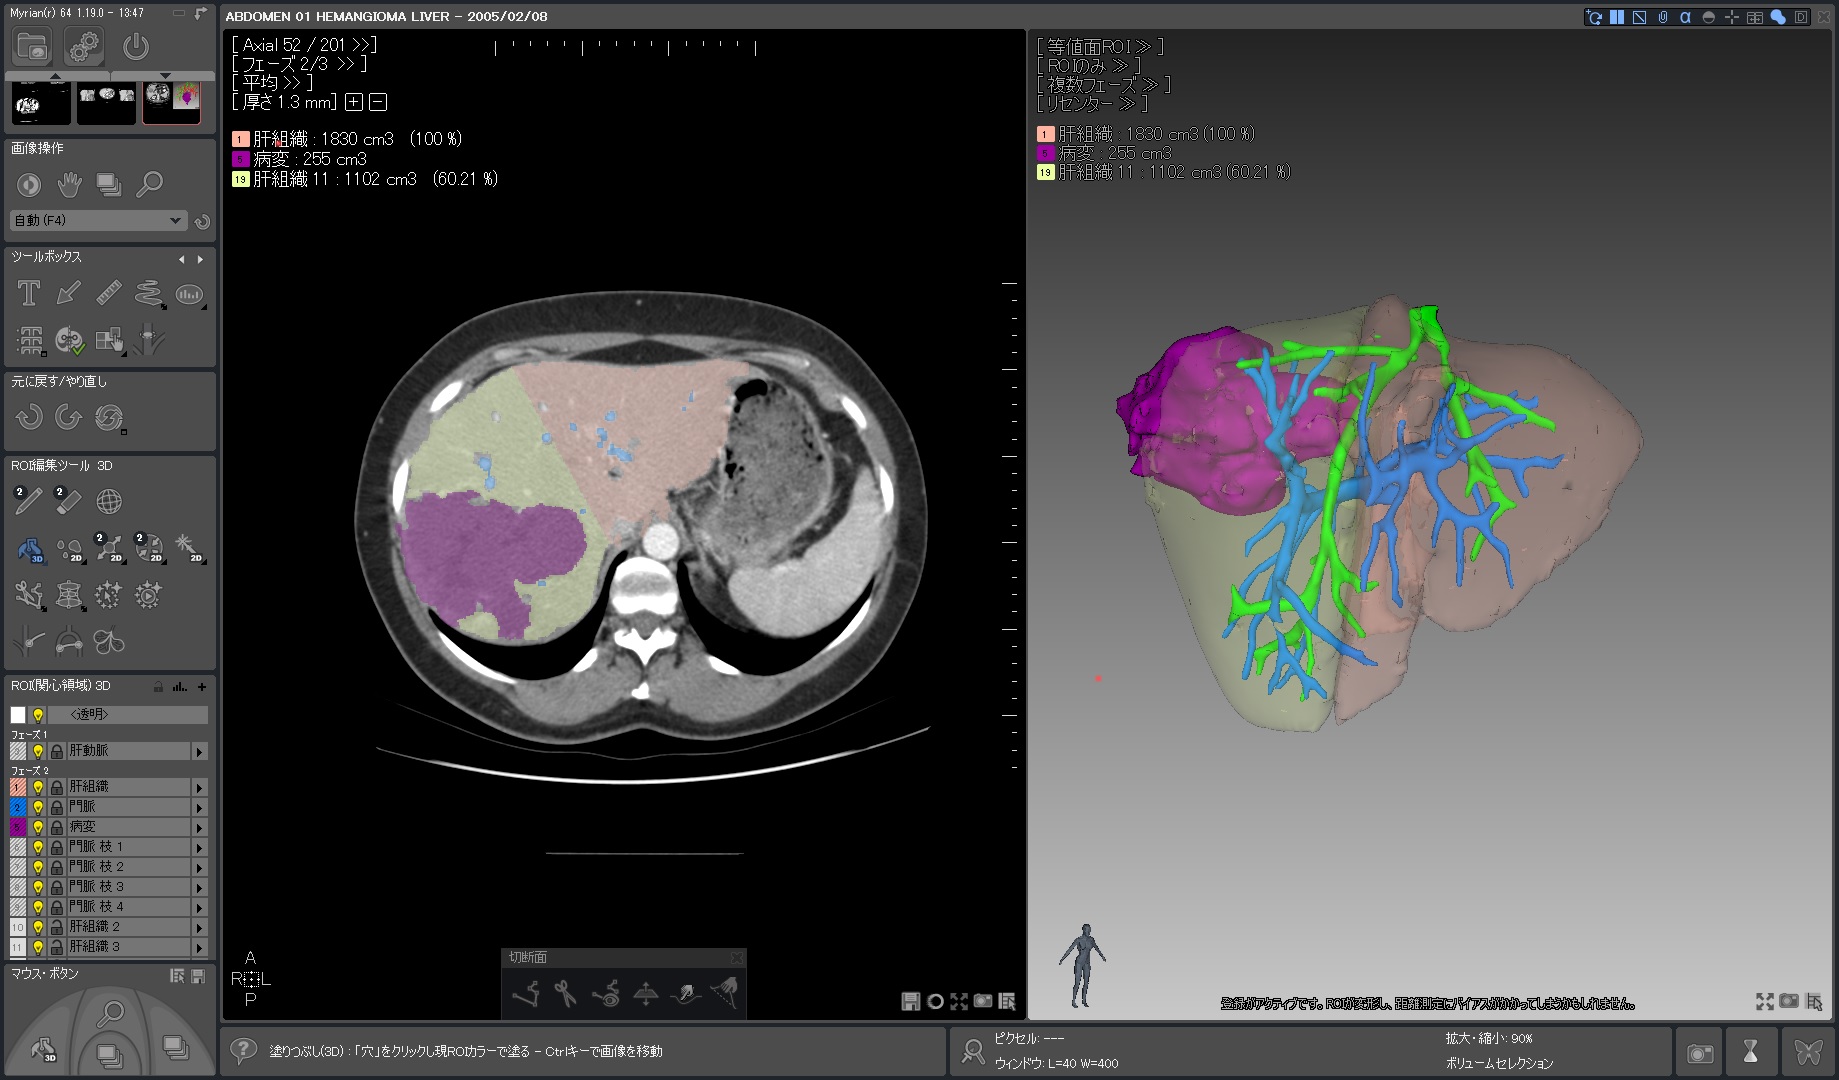

Myrian®XP-Liver 肝臓アプリケーション

世界的な実績と評価を得ている、肝臓解析と手術計画用ソフトウェア

独自に開発された、正確な非剛体レジストレーションと優れたセグメンテーション・アルゴリズムにより肝血管系、肝実質、腫瘍などを数秒で抽出します。

3D PDFによる立体表示ではコミュニケーションの向上に寄与するでしょう。

当製品は3D業界の先駆けとして、世界トップの施設で使用されています。

| 1.病変部領域 正常部領域の ワンクリック セグメンテーションと 体積表示 |

|

|---|---|

| 2.肝臓血管系の半自動抽出 |  |

| 3.血管支配域の表示 |  |

| 4.ヒストグラム解析 |  |

| 5.術前手術 シュミレーション |

|

|

|